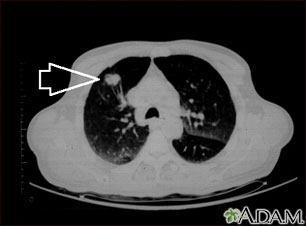

This is a CT scan of the upper lungs. This individual has a mass in upper part of the right lung (left side of picture).